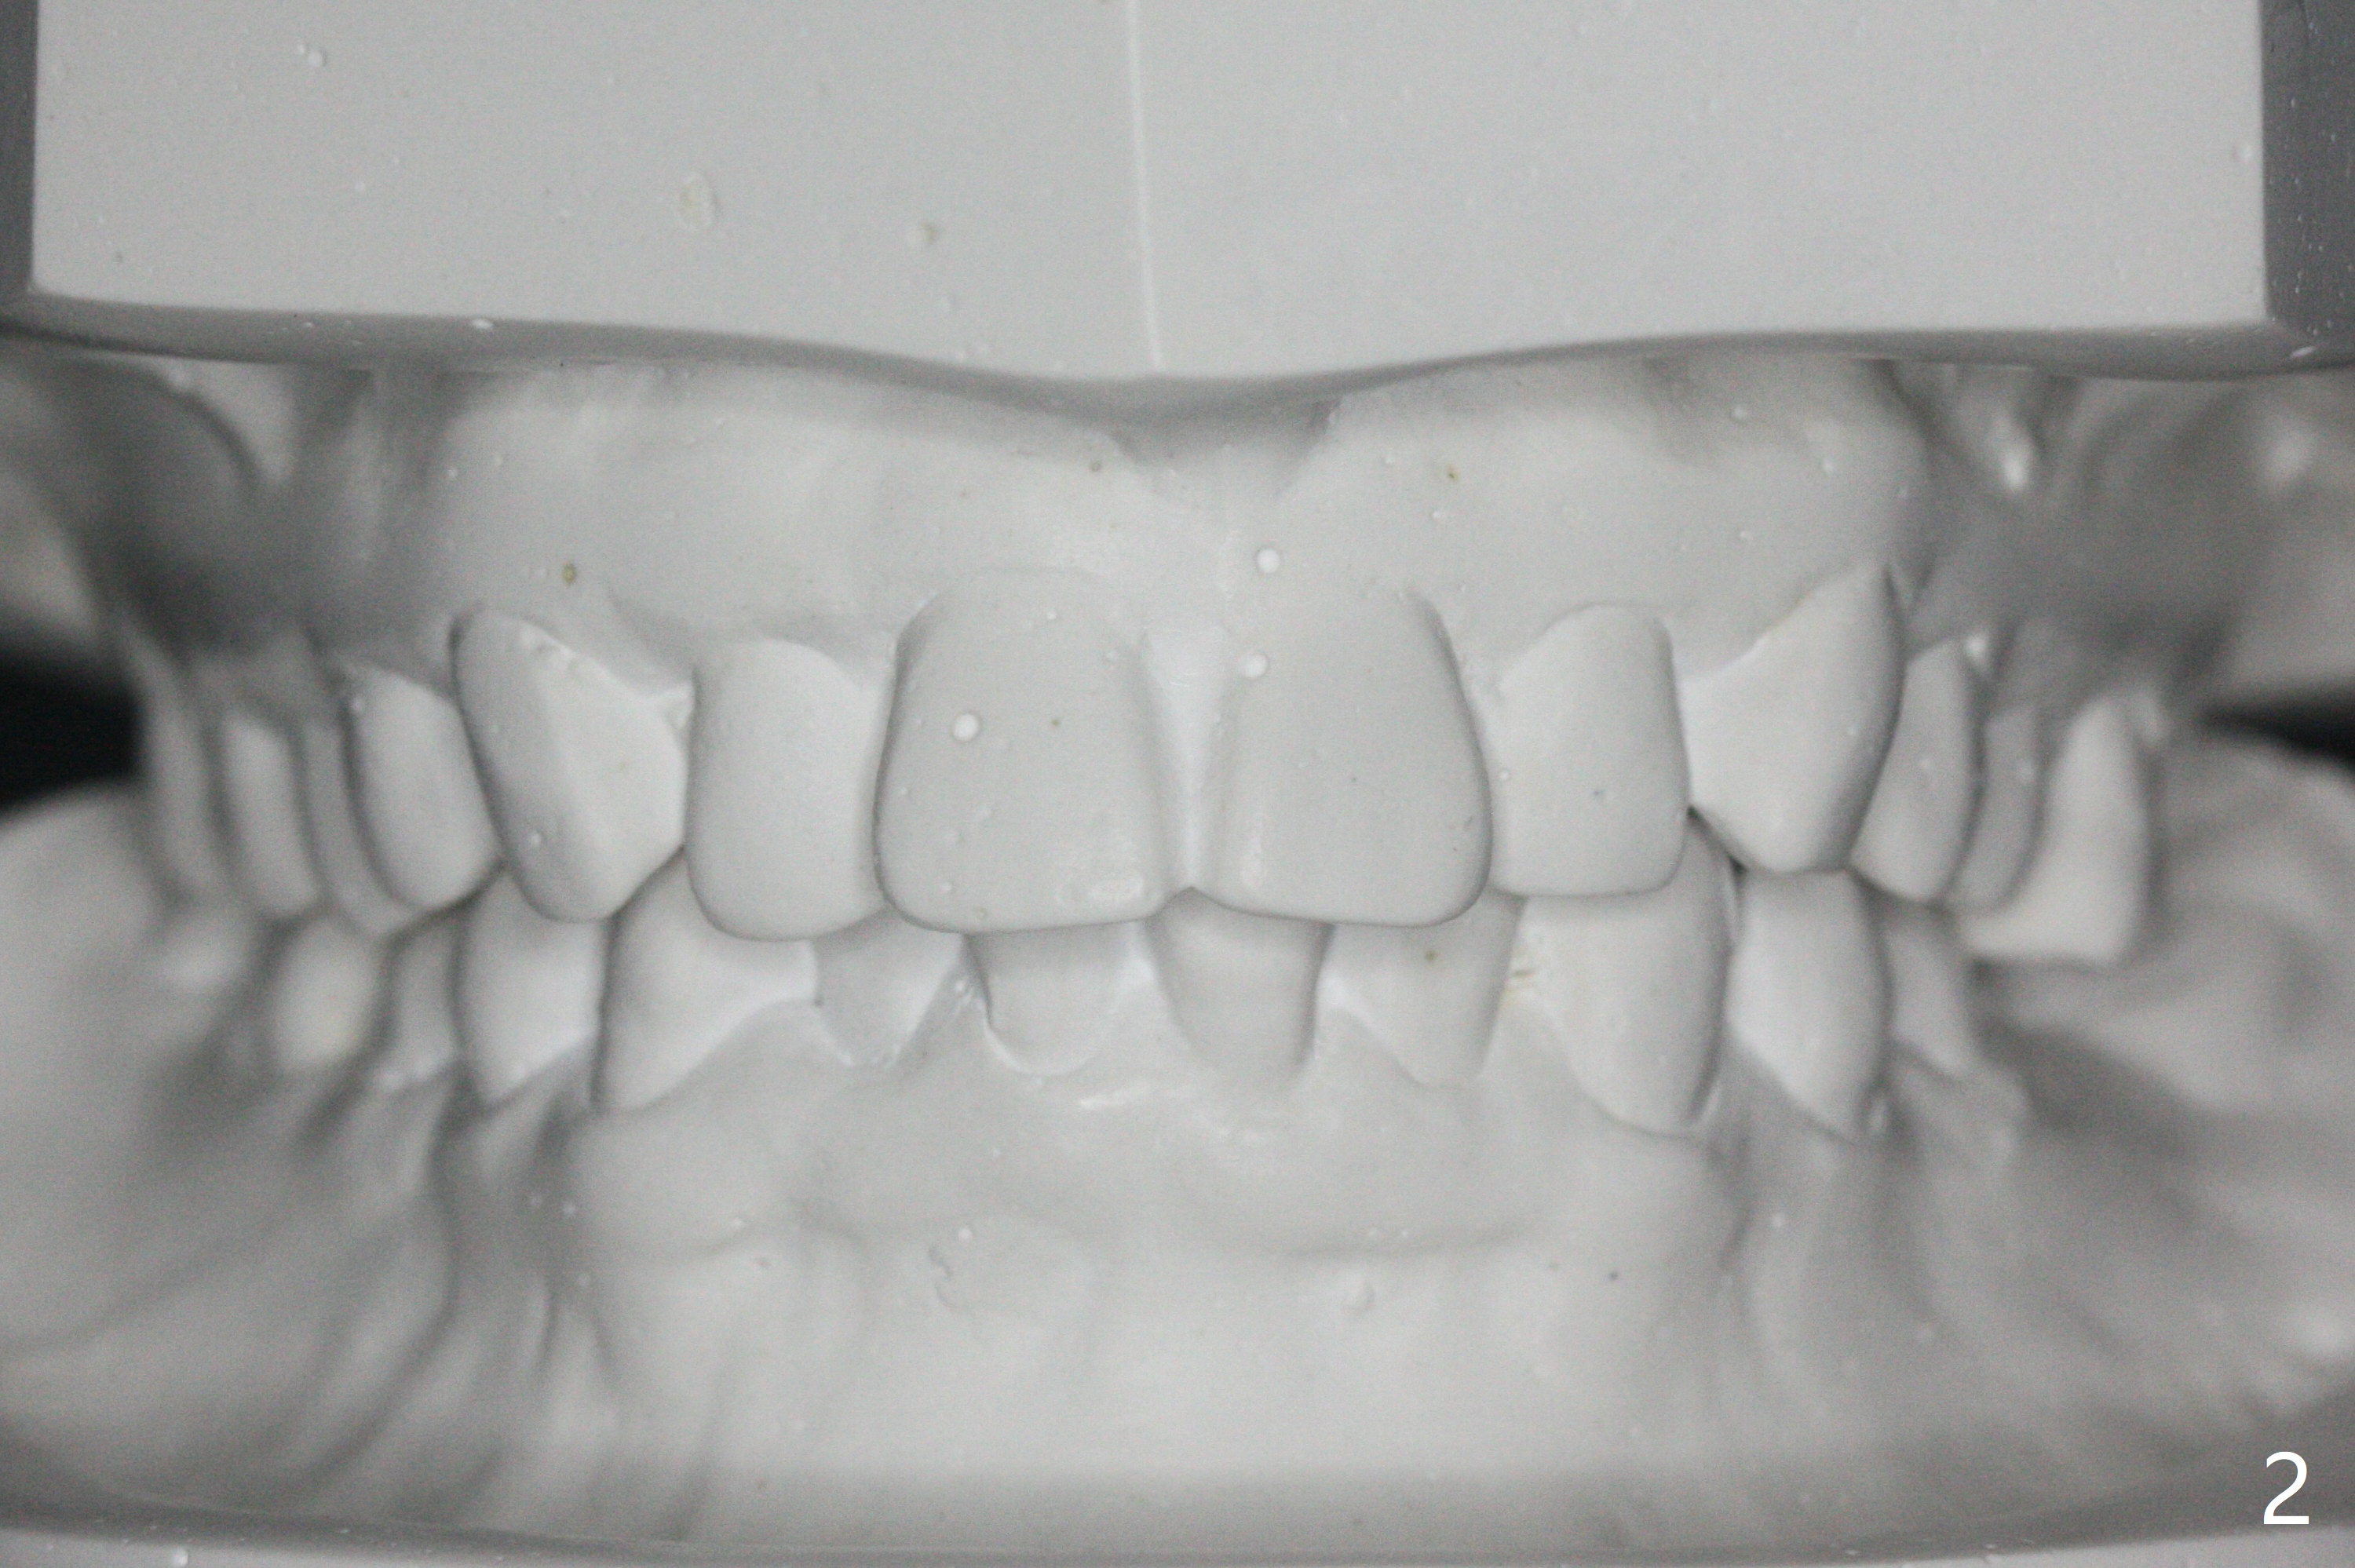

31岁女,牙周炎,安格氏二类错𬌗(图一至八),深洗后,同意牙齿矫正,但是要求保留左下智齿,前移7,8,取代6,左上6过度萌出(图三:箭头)。

初步计划:第一期安置矫正器,排列,建立正常前牙覆合覆盖,二类牵拉。尽量竖直左下7,8(图十一:白色轮廓);使用两个微型植体(图九:黑线(两个植体之间放置power chain(红线)))压入左上6(图十(圆圈:近中微型植体),与图三对比),为左下7近中移位(红色箭头)创造空间。

第二期在左下4和5之间植入微型植体作为支抗(图十一:红色),利用7远中长勾(粉红色)和橡皮筋,先让7平行近中移位,控制根torque。A 31-year-old woman with Class II Division I malocclusion requests orthodontic treatment without extraction of LL8. U8s and LL6 have been extracted with SRP. The 1st stage will be alignment , intrusion of UL6, upright of LL7 and 8 and correction of Class II malocclusion using double twin.